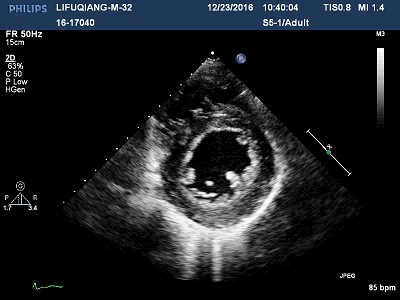

2016-11-23心超:

◆左房增大(46mm),左室增大(LVEDD 60mm),

◆左室壁整体收缩活动减弱(左室壁均匀性增厚,心肌内回声不均,LVEF 38%),

◆左室舒张功能减退 E/E`>12;

◆左室内多发占位(下壁心尖部2处、侧壁心尖部1处团块样中等回声,随血流甩动,有蒂连接室壁,大小分别为19*14mm、15*9mm、8*4mm);

◆右房增大(52*44mm),右室内径正常,TAPSE 16mm;

◆微量心包积液(左室后方房室沟内4mm无回声区)